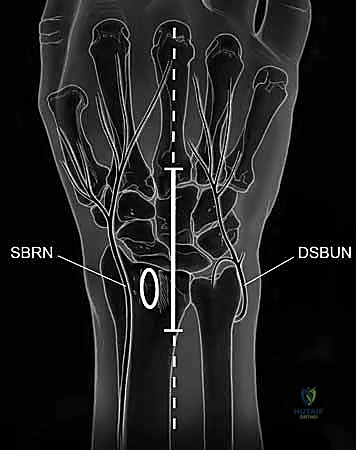

TECH FIG 1 • A. Axial image of dorsal wrist compartments with arrow indicating location for skin incision over third compartment. B. Skin incision centered over third dorsal compartment with superficial branch of the radial nerve (SBRN) and dorsal sensory branch of the ulnar nerve (DSBUN). Oval indicates tubercle of Lister. (Copyright © Mayo Clinic.)

> **Surgical Warning:** As you make your skin incision, be acutely aware of the **dorsal sensory branch of the ulnar nerve (DSBUN)**. This nerve runs subcutaneously along the ulnar side of the wrist and is highly vulnerable. Use careful, sharp dissection, identifying and protecting it with fine vessel loops or retractors. Similarly, the superficial branch of the radial nerve (SBRN) is on the radial side, though less likely to be in our direct field here.